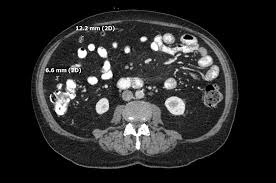

benign multicystic peritoneal mesothelioma b a figure 1 computed tomography axial image results. (ct) of abdomen and pelvis showed a large multicystic mass of the spleen. Plain computed tomography axial image showing a hypodense mass; Søreide ja, søreide k, körner h, et al. A rare condition in an uncommon gender muhammads.khurram, 1 hamadullahshaikh, 2 uqbakhan, 1 jacobedens, 1 wardaibrar, 1

Most often the growth is localized, being a single tumor larger than the diffuse small tumors that. Bmpm usually consists multiple cysts but it could be unilocular. benign mesotheliomas also have been commonly reported to develop from the pleura. Although many therapeutic approaches have been used, complete cytoreductive. Usually benign tumors, but there are some cases where malignant cells are mixed with benign cells. benign cystic mesothelioma of the peritoneum (bcm) is an uncommon lesion with some 130 cases reported since the first case described by smith and mennenmeyer in 1979. Plain computed tomography axial image showing a hypodense mass; The tumors have a distinctive cell type and grow in multiple cysts that are usually benign but in rare cases become malignant.